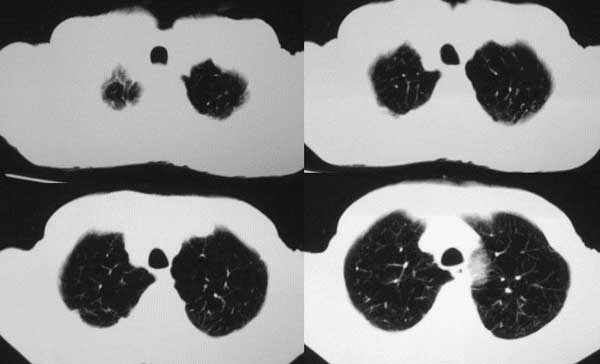

患者,男79岁,左侧肾癌术后5个月。近三个月,咳嗽时有痰中带血。

本例病人肺内多发结节灶、双侧肋骨破坏、胸椎椎体及椎弓破坏应是肾癌转移。请大家分析气管内结节灶性质?另外还得麻烦领导给删掉那多余的那幅图。谢谢了!

双肺多发结节状影,腹膜后见肿大淋巴结,支持肾ca转移

双肺内多发结节影是转移灶没问题,气管内的还应该商榷

肺内 肋骨 椎体转移已确定,气管内阴影不象结节,气管内壁无增生,显示层面只有一层,纵隔窗见不到,多考虑粘痰核.